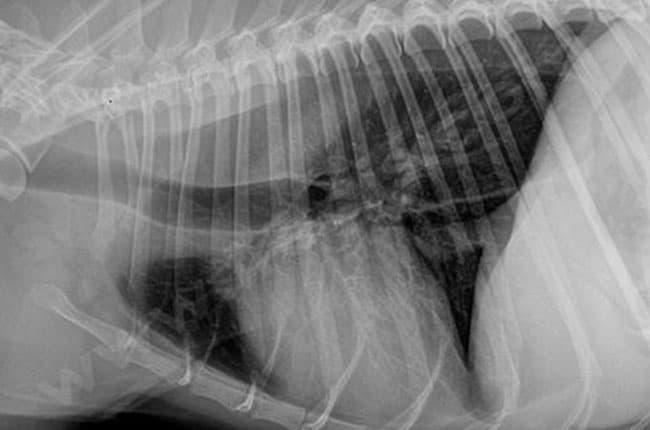

Il faut évaluer le larynx et ses mouvements durant la respiration. Pour cela, un examen sous fibroscopie (avec une petite caméra) est réalisé avec une anesthésie très légère. Des radiographies pulmonaires et des analyses sanguines sont également réalisées.

Les complications possibles incluent une infection (qui est le plus souvent superficielle et se traite facilement), un lâchage des prothèses nécessitant une autre chirurgie, et surtout une pneumonie par aspiration. Ces pneumonies sont dues au passage d’aliment dans la trachée. Elles peuvent être plus importantes si les chiens ont déjà des problèmes de déglutition. La sévérité de ses pneumonies sont variables : parfois limitées, elles ne sont même pas visibles sans radiographie (le chien agit totalement normalement et la guérison se fera toute seule) ; d’autres fois elles sont très sérieuses et nécessitent une hospitalisation en soins intensifs pendant plusieurs jours avec des traitements importants.